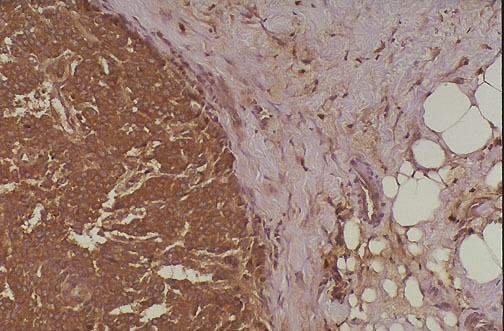

| This is positive immunohistochemical staining for cathepsin D (an acidic lysosomal protease) in a breast carcinoma. Note the cytoplasmic staining of the neoplastic cells on the left, as well as staining in the stroma to the right. There is a correlation between cathepsin D positivity and presence of metastases (particularly lymph nodes). Cathepsin D staining is more likely to be observed in non-ductal carcinomas. |